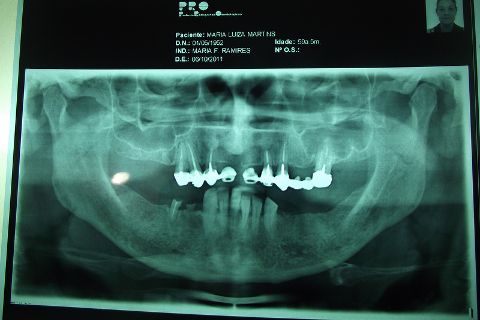

PEDODOS EX; TOMOGRÁFIA,PANORAMICA,EX:COMPLEMENTARES

REALIZAÇÃO DO PROCEDIMENTO :04/11/2011